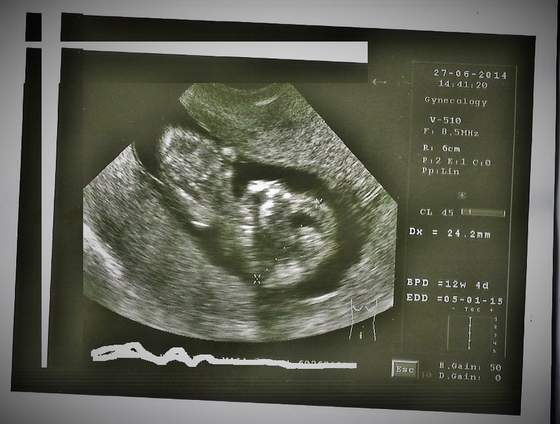

Ana, ale przecież na tym etapie u obu płci jeszcze sterczy nub między nóżkami, może idź na inne USG żeby się nie zadręczać? Na tych zdjęciach niestety nic nie widać :-(